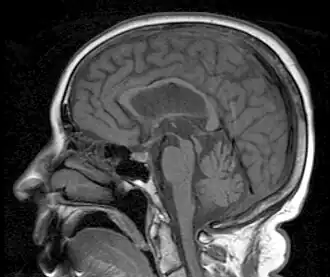

Een sagittale MRI-afbeelding toont atrofie in het mesencephalon kenmerkend voor PSP.

Progressieve supranucleaire parese[1] of progressieve supranucleaire paralyse[2] (PSP) wordt ook wel genoemd syndroom van Steele-Richardson-Olszewski. De aandoening begint doorgaans tussen het 50e en 80e levensjaar en wordt gekenmerkt door parkinsonisme, gestoorde oogbewegingen en dementie. Vaak gaat de patiënt ook naar beneden of boven kijken in plaats van recht vooruit en neemt de loopsnelheid af. Ook vallen zij vaak en hebben ze regelmatig slikstoornissen.